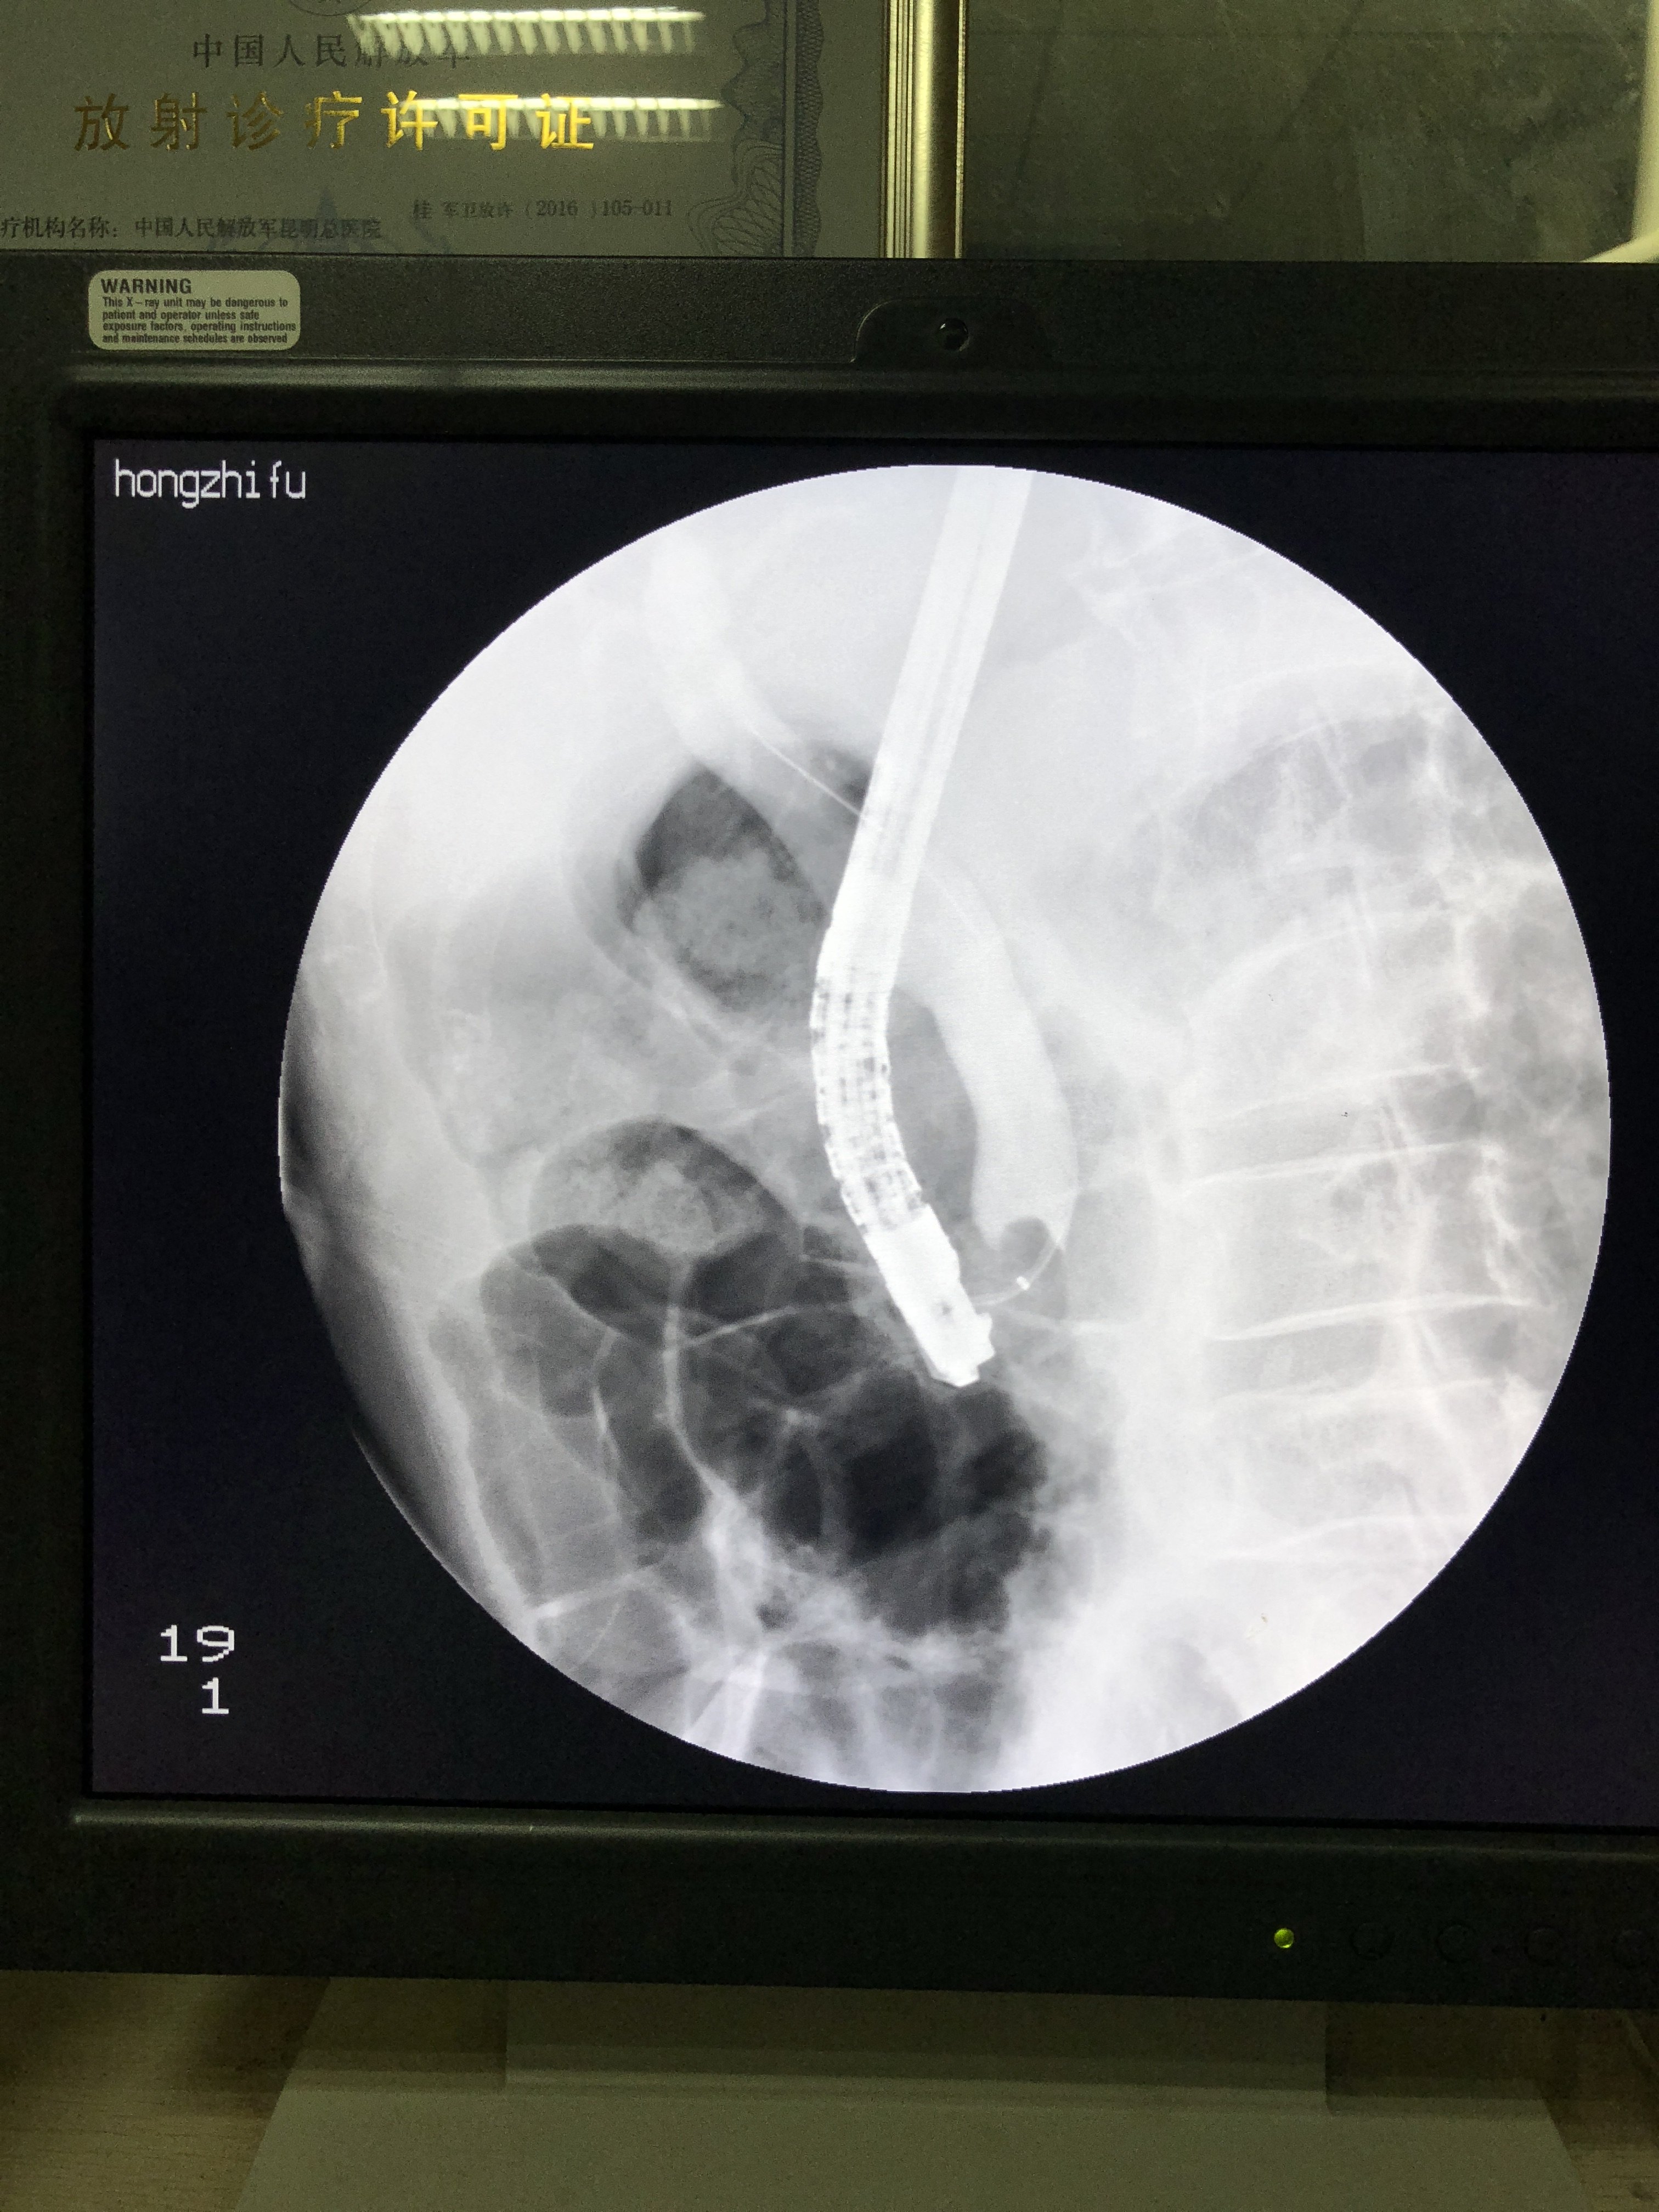

胆管下端狭窄即缩窄性乳头炎伴胆管扩张并

3024x4032 - 2647KB - JPEG

3024x4032 - 3378KB - JPEG

3024x4032 - 2260KB - JPEG